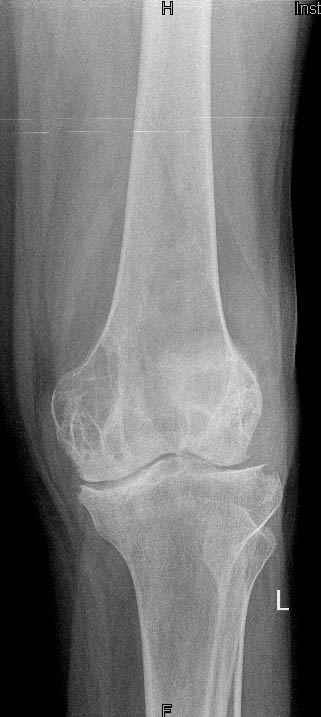

Коллеги!Окажите, пожалуйста, консультативную помощь.Мужчина, 41 год, 15 лет состоит на учете по поводу ревматоидного полиартрита, гормонзависимый (преднизолон получает нерегулярно). В процесс вовлечены крупные и мелкие суставы. 01.01.06 - без травмы наступил патологический перелом на границе н/3-с/3 бедра (перелом на фоне кистозных изменений?) Биопсия из зоны перелома - <реактивные изменения в очаге перелома>, без признаков опухоли. На рентгенограммах, помимо перелома, кистозные изменения на мыщелках б/берцовой кости и мыщелке бедра с другой стороны. До травмы со стороный коленных суставов был болевой синдром, функция практически в полном объеме. Какие будут предложения по тактика лечения перелома и кист на противоположом бедре? Заранее благодарю! С уважением, А.В.Владзимирский Донецкий НИИ травматологии и ортопедии Донецк, Украина